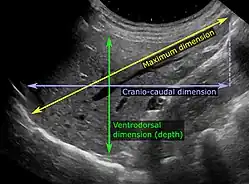

Chez les patients dont les tests de la fonction hépatique sont perturbés, l'échographie peut montrer une augmentation de la taille du foie (hépatomégalie), une réflectivité accrue (qui pourrait, par exemple, indiquer une cholestase), des maladies de la vésicule biliaire ou des voies biliaires ou une tumeur du foie. L'échographie des tumeurs hépatiques comporte deux étapes : la détection et la caractérisation[réf. nécessaire]. La détection des tumeurs est basée sur les performances de la méthode et doit inclure des informations morphométriques (dimensions sur trois axes, volume) et des informations topographiques (nombre, emplacement spécifiant le segment hépatique et le lobe/lobes). La spécification de ces données est importante pour la stadification des tumeurs hépatiques et le pronostic[réf. nécessaire]. La caractérisation de tumeur est un processus complexe basé sur une somme de critères menant vers la définition de nature de tumeur. Souvent, d'autres procédures de diagnostic, notamment interventionnelles, ne sont plus nécessaires. La caractérisation tumorale par la méthode échographique sera basée sur les éléments suivants : consistance (solide, liquide, mixte), échogénicité, aspect structurel (homogène ou hétérogène), délimitation du parenchyme hépatique adjacent (capsulaire, imprécis), élasticité, effet de rehaussement acoustique postérieur, la relation avec les organes ou structures de voisinage (déplacement, invasion), la vascularisation (présence et caractéristiques en échographie Doppler et en échographie de contraste (ECUS)[réf. nécessaire].

L'échographie des reins est essentielle dans le diagnostic et la prise en charge des maladies rénales. Les reins sont facilement examinés et la plupart des modifications pathologiques des reins se distinguent par échographie[9].